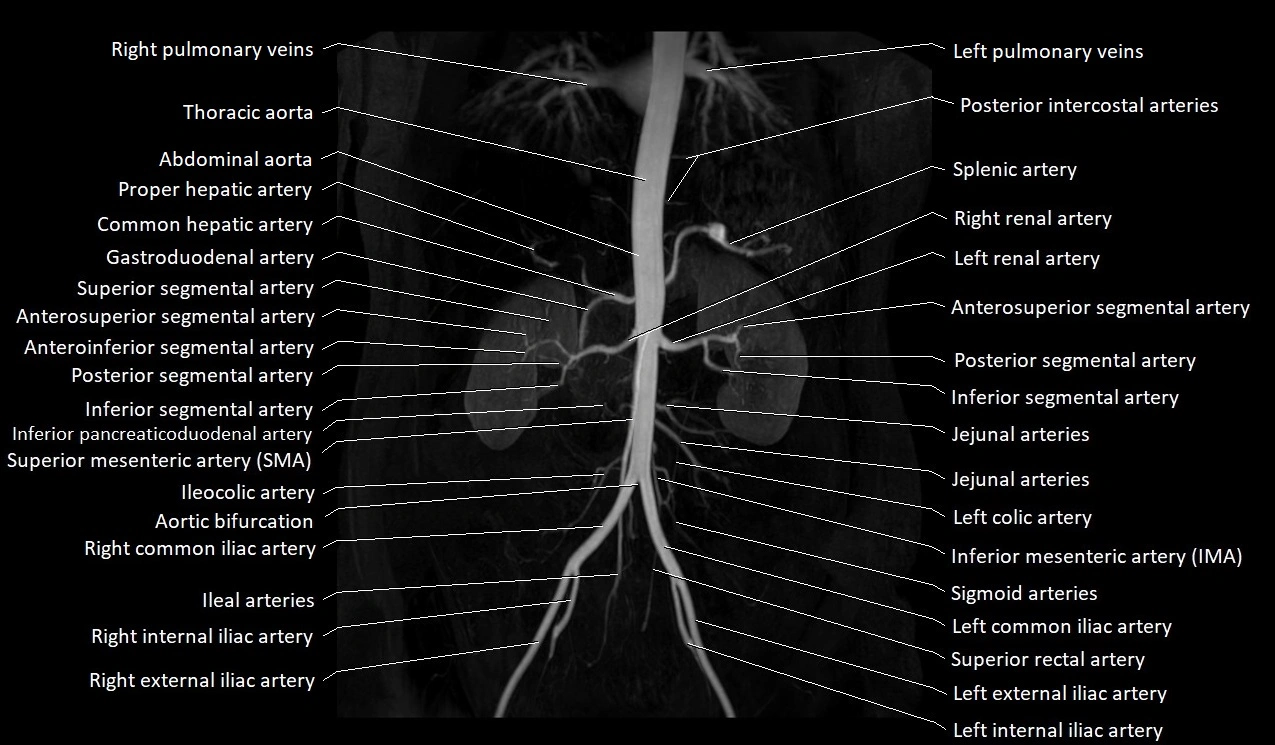

MRA Pelvis with Gadolinium:

-

Clearly delineates the origin, course, and anastomoses of the accessory obturator artery

Identifies connection with inferior epigastric artery, external iliac artery, or obturator artery

Excellent for detecting vascular variants prior to surgery

Useful in mapping pelvic vasculature in trauma, tumor embolization, or preoperative planning